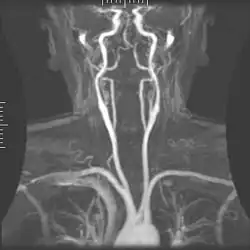

Angiografia tętnic szyjnych

Angiografia tętnic szyjnych jest wykorzystywana w celu wykrycia zwężeń tętnic szyjnych i wynikających z niego następstw. W badaniu wykorzystywane są przezczaszkowe badania dopplerowskie, ocena ultrasonograficzna oraz analiza komputerowa lub rezonans magnetyczny[13]. Arteriografia jest metodą tracąca obecnie na popularności ze względu na rozwój innych, czułych i nieinwazyjnych metod, takich jak angio-MR, angio-TK czy duplex-scan. W przypadku badań chorych ze zwężeniem ICA, metoda ta została zupełnie wyparta przez duplex-scan, który to jest bardziej opłacalną metodą diagnostyczną[14].